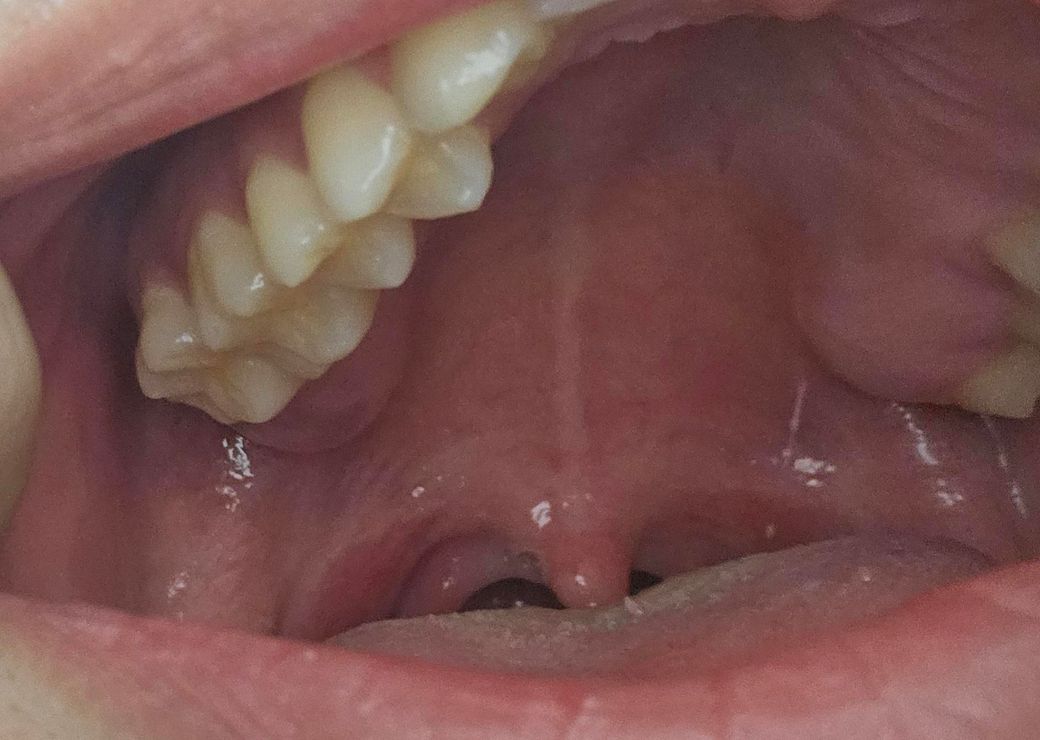

두번째는 사랑니 나중에 뽑을거 같습니다

• 2번 째 사진